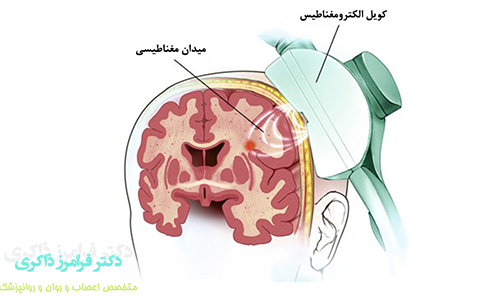

امواج مغناطیسی که دستگاه TMS تولید می کند از پوست و مو و استخوانهای جمجمه عبور می کند وارد مغز می شود و پس از برخورد با سطح قشری مغز به امواج الکتریکی تبدیل می شود این جریان های الکتریکی بر سلول های مغز اثر می گذارد و باعث انتشار انتقال دهنده های عصبی مانند سروتونین، نور اپی نفرین و دوپامین می شوند.

در واقع TMS به ما امکان برقراری ارتباط مستقیم با نورون های موجود در مغز را به زبان خودشان (الکتریسیته) می دهد. فرکانس و مدت زمان امواج توسط دستگاه TMS قابل کنترل است. بسیار مهم است که TMS نقطه ی مناسبی را در مغز شما هدف قرار دهد در غیر این صورت ممکن است منافعی را که واقعا به آن احتیاج دارید، دریافت نکنید.